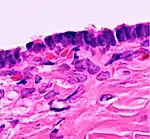

Histopathology

In case an ovarian cyst is surgically removed, a more definite diagnosis can be made by histopathology:

| Type | Subtype | Typical microscopy findings | Image |

| Cystadenoma | Serous cystadenoma | Cyst lining consisting of a simple epithelium, whose cells may be either:[21]

|

![]() |